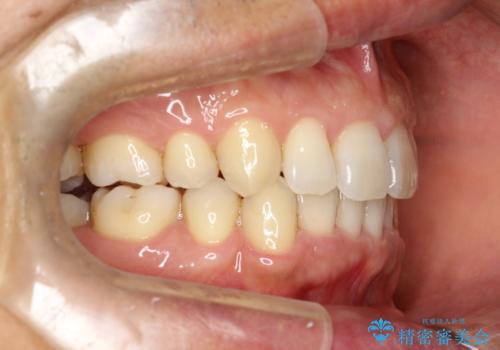

- 以前、上下左右4本抜いてワイヤー矯正をしていた方で、後戻りで下の前歯のガタガタを気にして来院されました。

マウスピース矯正にて、下の歯はIPR(歯と歯の間を削る)を入れることでガタガタの改善、咬み合わせの深さも改善をはかる治療計画をたてました。

歯と歯の間を削って隙間を作って矯正をしています。

保定装置(後戻り防止のための装置)は、基本的にはマウスピースタイプをお渡ししているのですが、患者様のご希望で取り外ししないタイプを希望されたので、前歯の裏側を細いワイヤーで固定(ボンディングリテーナー)を作成しています。